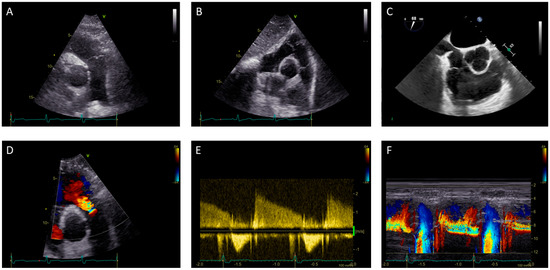

1.1. Pulmonary Valve Stenosis: Role of Echocardiography

1.2. Pulmonary Valve Regurgitation: Role of Echocardiography

1.3. Right Ventricle Assessment in Pulmonary Stenosis and Regurgitation: Role of Echocardiography